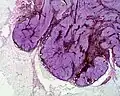

Micrograph of a blue nevus showing the characteristic pigmented melanocytes between bundles of collagen. H&E stain